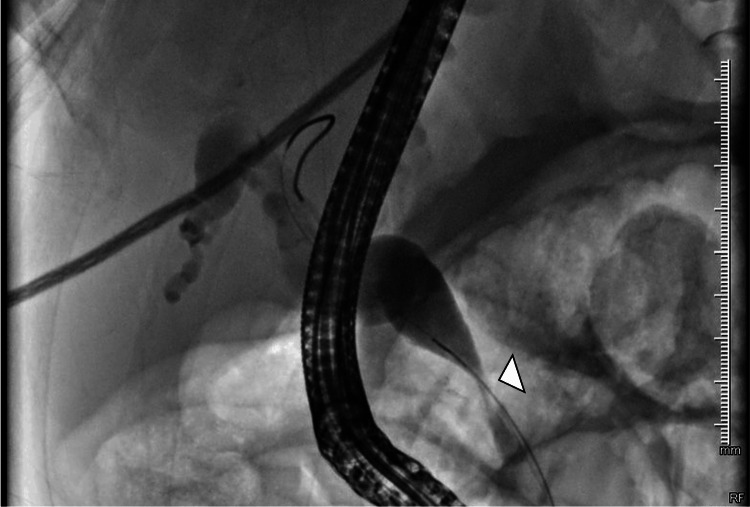

Given the clinical and imaging findings, a diagnostic and therapeutic ERCP was indicated, demonstrating a distal CBD stricture; a 10 Fr × 12 cm biliary stent was placed (Figures 4, 5).